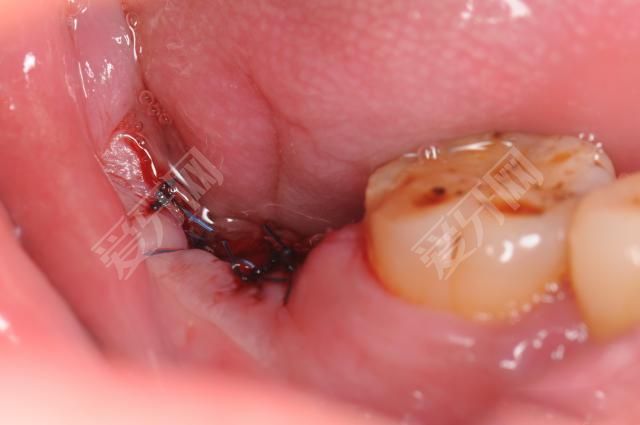

植牙后能做核磁共振嗎

3.術(shù)后一個(gè)半月內(nèi)不宜吃過硬、過韌的食物,以防種植體受力過大。種植體最怕在愈合過程中經(jīng)常受力。所以在種植區(qū),活動(dòng)義齒盡量不要戴。

4.種植牙防止外力損傷,一旦損傷應(yīng)立即聯(lián)系牙醫(yī)。

5.良好的口腔衛(wèi)生習(xí)慣是種植牙成功的重要保證,因此患者應(yīng)及時(shí)進(jìn)行有效的口腔清潔。術(shù)后兩周內(nèi),飯后及時(shí)漱口,每天用漱口水漱口幾次,避免感染。修復(fù)后應(yīng)定期洗牙,早晚用軟毛牙刷和牙線清洗種植體一次。